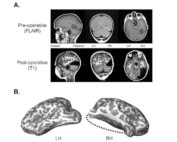

La operación, cuando tenía 6 años y 10 meses, eliminó el lóbulo occipital completo de [...]